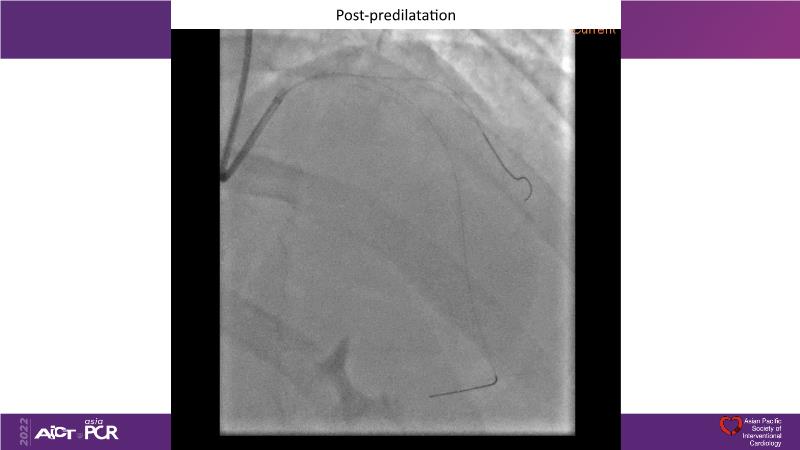

Consult this session to understand the technology and scientific evidence of the novel sirolimus drug-coated balloon, to learn its utility for PCI in a variety of lesion and patient subsets and to understand the evidence and outcomes in real-world patients.

- To understand the technology and scientific evidence of the novel sirolimus drug-coated balloon (SDCB)

- To learn the utility of the DCB for PCI in a variety of lesion and patient subsets